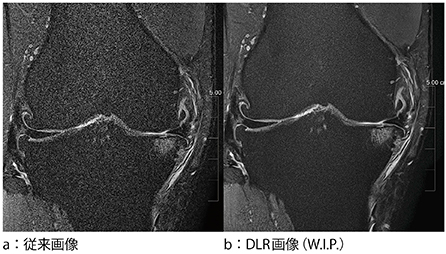

長時間撮像は,患者さんの体動により安定した描出が困難なケースが多く,一般的な検査として実施することは難しい。そこで,高分解能撮像を短時間に実現すべく検討しているのが,“Deep Learning Reconstruction”である。ディープラーニングの学習に関する基本的な原理に関してはCTと同様である。ノイズを学習させることで,MRIのさまざまなシーケンス,コントラストへの対応が可能であり,画質改善だけでなく,解析結果の安定性向上などにも期待されている(図2)。

図2 膝関節2D 1mmスライス画像(撮像時間1:07)での比較